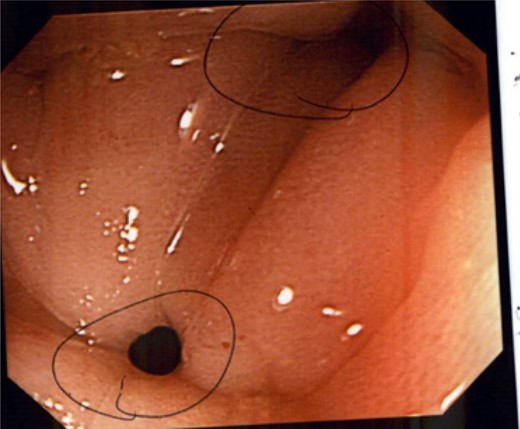

Following discharge, the patient re-presented to the clinic 2 years later complaining of increasing discharge from her rectal stump with a simultaneous decrease in colostomy output. A sigmoidoscopy demonstrated two fistulae within the rectal stump, and a CT confirmed a communication between the stump and proximal small bowel (Fig. 2). She has elected for conservative management of her condition.

Colonoscopy demonstrating several fistulae into the anal pouch.